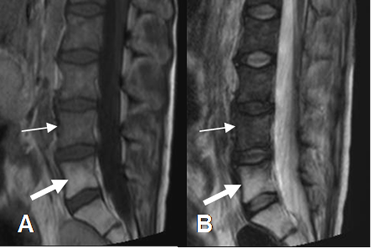

Por imagen la SI de la medula es hiperintensa en T1 y T2, por predominio de la medula grasa. (Fig 17 A y 17 B).

Fig 17 A. Reconversión a medula amarilla.

A: RM sagital en T1 y B: RM sagital en T2. Alteración en la SI de los cuerpos vertebrales L2, L3 y L4 siendo hipointensos por reconversión a medula roja (Flechas delgadas). Además las vértebras L5 y S1, son hiperintensas por depleción celular, secundaria a radioterapia por neoplasia de cérvix. (Flechas gruesas).